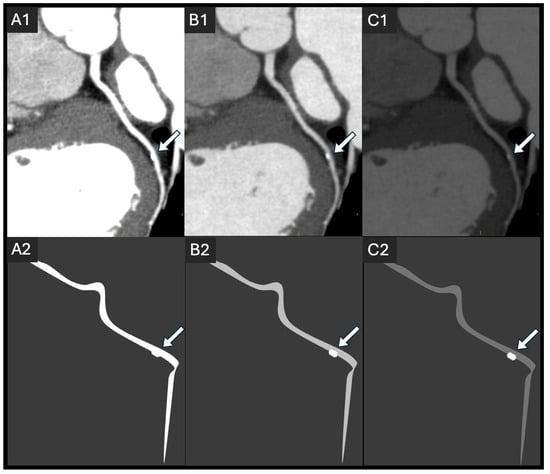

4.1. Tube Kilovoltage Peak (kVp)

- Tan, S.K.; Yeong, C.H.; Raja Aman, R.R.A.; Ng, K.H.; Abdul Aziz, Y.F.; Chee, K.H.; Sun, Z. Low tube voltage prospectively ECG-triggered coronary CT angiography: A systematic review of image quality and radiation dose. Br. J. Radiol. 2018, 91, 20170874. [Google Scholar] [CrossRef]

- Bischoff, B.; Hein, F.; Meyer, T.; Hadamitzky, M.; Martinoff, S.; Schömig, A.; Hausleiter, J. Impact of a reduced tube voltage on CT angiography and radiation dose: Results of the PROTECTION I study. JACC Cardiovasc. Imaging 2009, 2, 940–946. [Google Scholar] [CrossRef]

- Zhang, Q.; Mi, H.; Shi, X.; Li, W.; Guo, S.; Wang, P.; Suo, H.; Wang, Z.; Jin, S.; Yan, F. Higher Iodine Concentration Enables Radiation Dose Reduction in Coronary CT Angiography. Acad. Radiol. 2021, 28, 1072–1080. [Google Scholar] [CrossRef]

- Yin, W.H.; Lu, B.; Gao, J.B.; Li, P.L.; Sun, K.; Wu, Z.F.; Yang, W.J.; Zhang, X.Q.; Zheng, M.W.; McQuiston, A.D. Effect of reduced x-ray tube voltage, low iodine concentration contrast medium, and sinogram-affirmed iterative reconstruction on image quality and radiation dose at coronary CT angiography: Results of the prospective multicenter REALISE trial. J. Cardiovasc. Comput. Tomogr. 2015, 9, 215–224. [Google Scholar] [CrossRef]